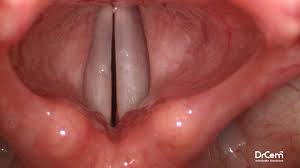

1️⃣ Ön burun kanaması (anterior epistaksis)

-

En sık görülen tiptir (%80–90)

Kanama burun deliklerinden dışarı akar

Genellikle hafif ve kontrol edilebilir

Çoğu çocuk ve gençte görülür

Nedeni:

Burnun ön kısmındaki Kiesselbach pleksusu (ince ve yüzeyel damar ağı)

Risk:

✔️ Düşük

✔️ Evde bile durdurulabilir